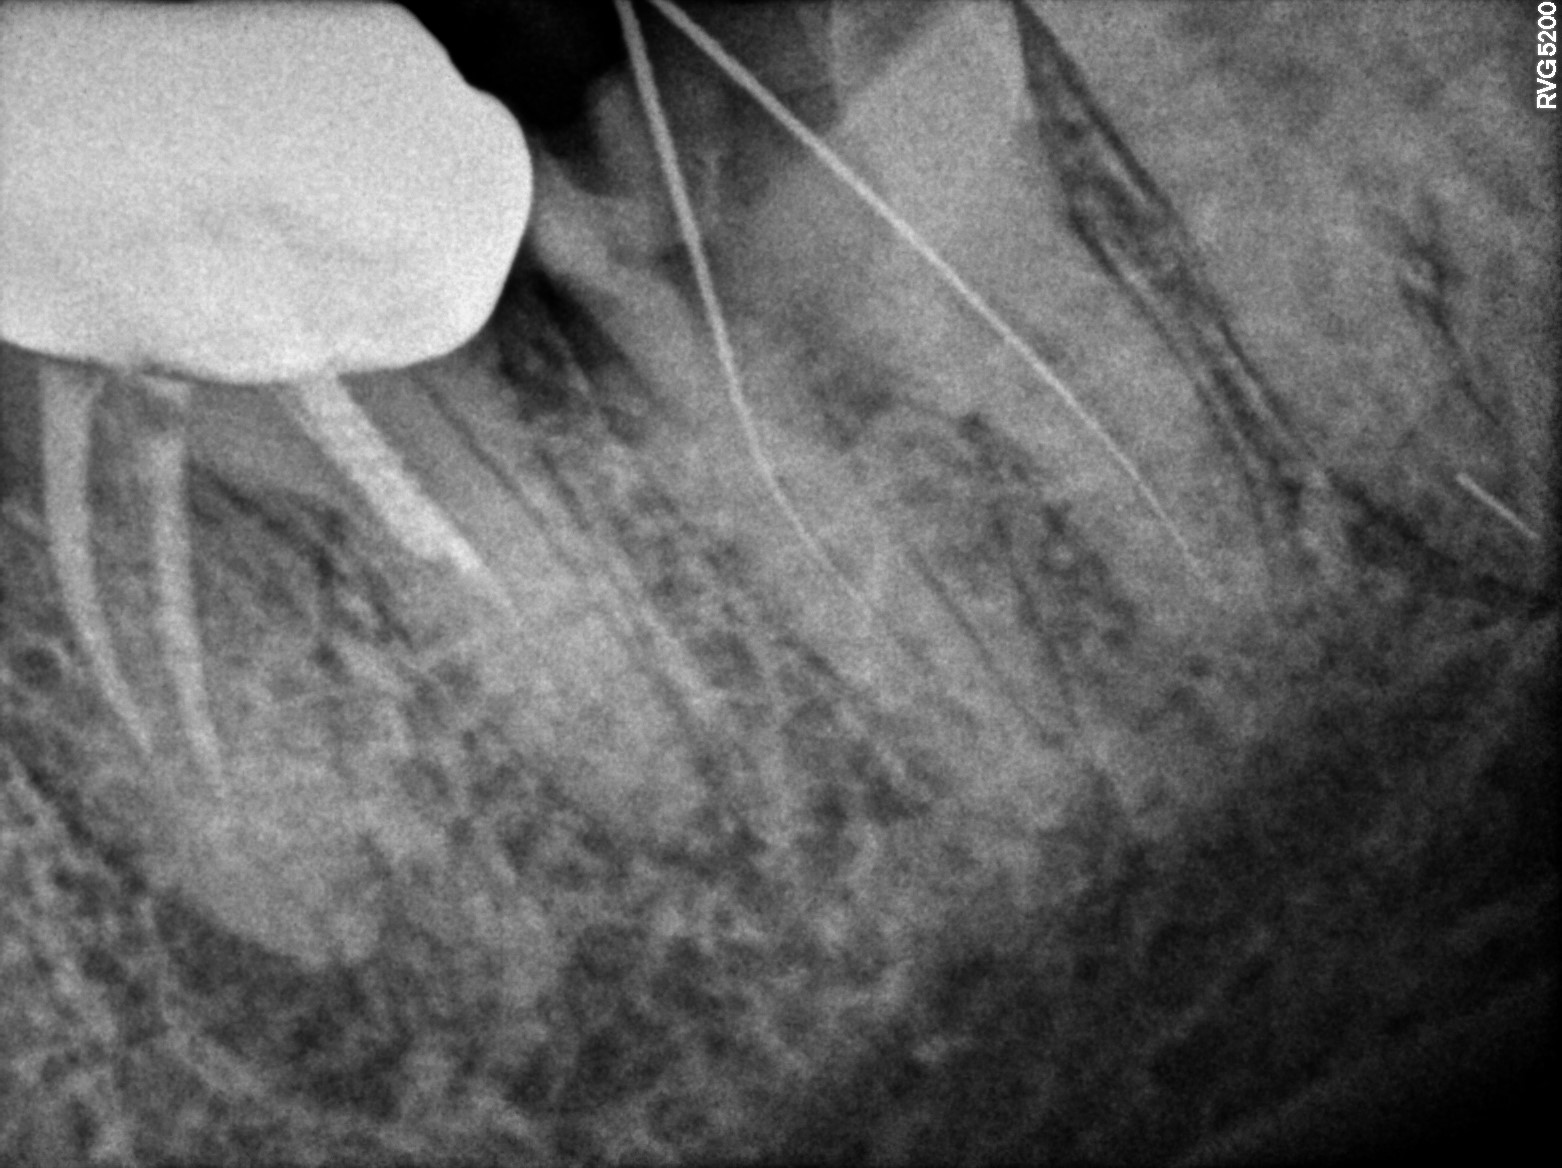

Dental Radiographs FHIR: DocumentReference · LOINC 24641-7

R55.jpg

24641-7